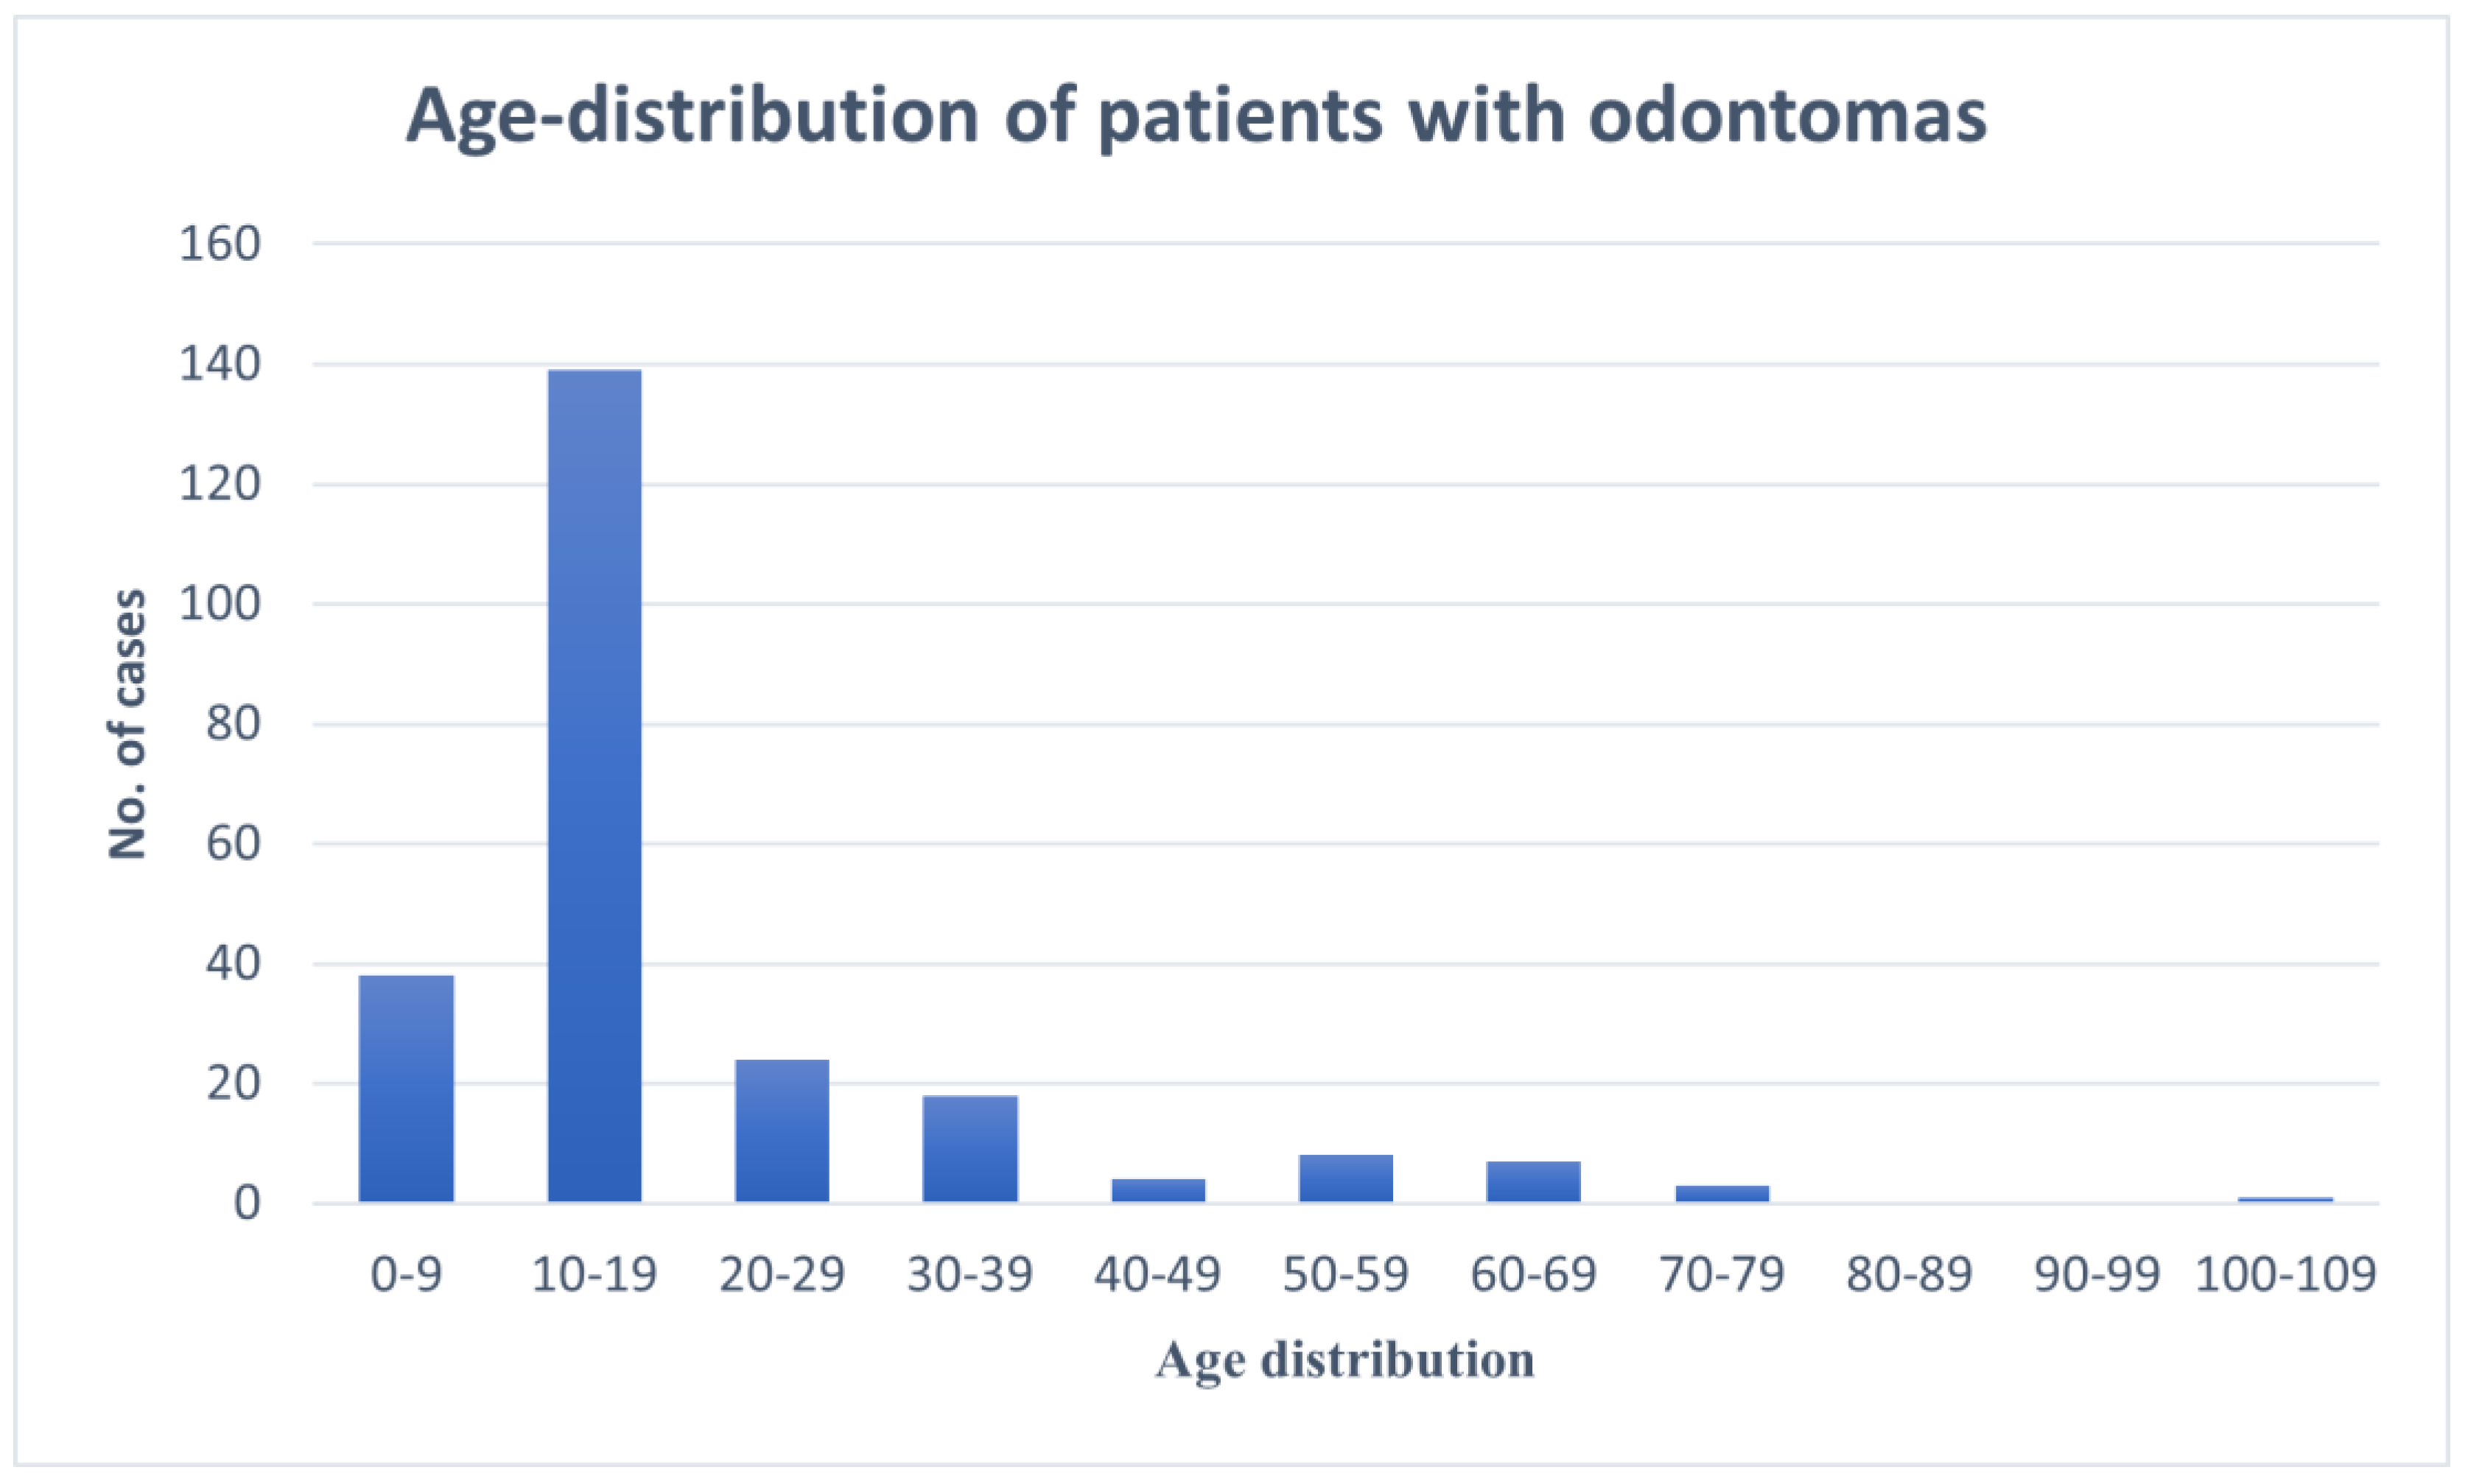

3. Results

3.1. Clinical, Radiographic, and Pathologic Characteristics

| Age Distribution (Years) | |

| 0–9 | 38 |

| 10–19 | 139 |

| 20–29 | 24 |

| 30–39 | 18 |

| 40–49 | 4 |

| 50–59 | 8 |

| 60–69 | 7 |

| 70–79 | 3 |

| 80–89 | 0 |

| 90–99 | 0 |

| 100–109 | 1 |